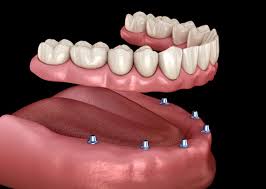

Transforming Smiles with Trusted Care – From Braces to Implants, Experience Dental Excellence with Us in Tirupati

We provide comprehensive dental care using modern techniques and advanced technologies. Whether you'... re looking for braces, cosmetic smile corrections, or full-mouth implants, our team delivers precise, comfortable, and long-lasting treatments that restore confidence and oral health. Your smile is in safe hands with our expert dental care professionals. Read more